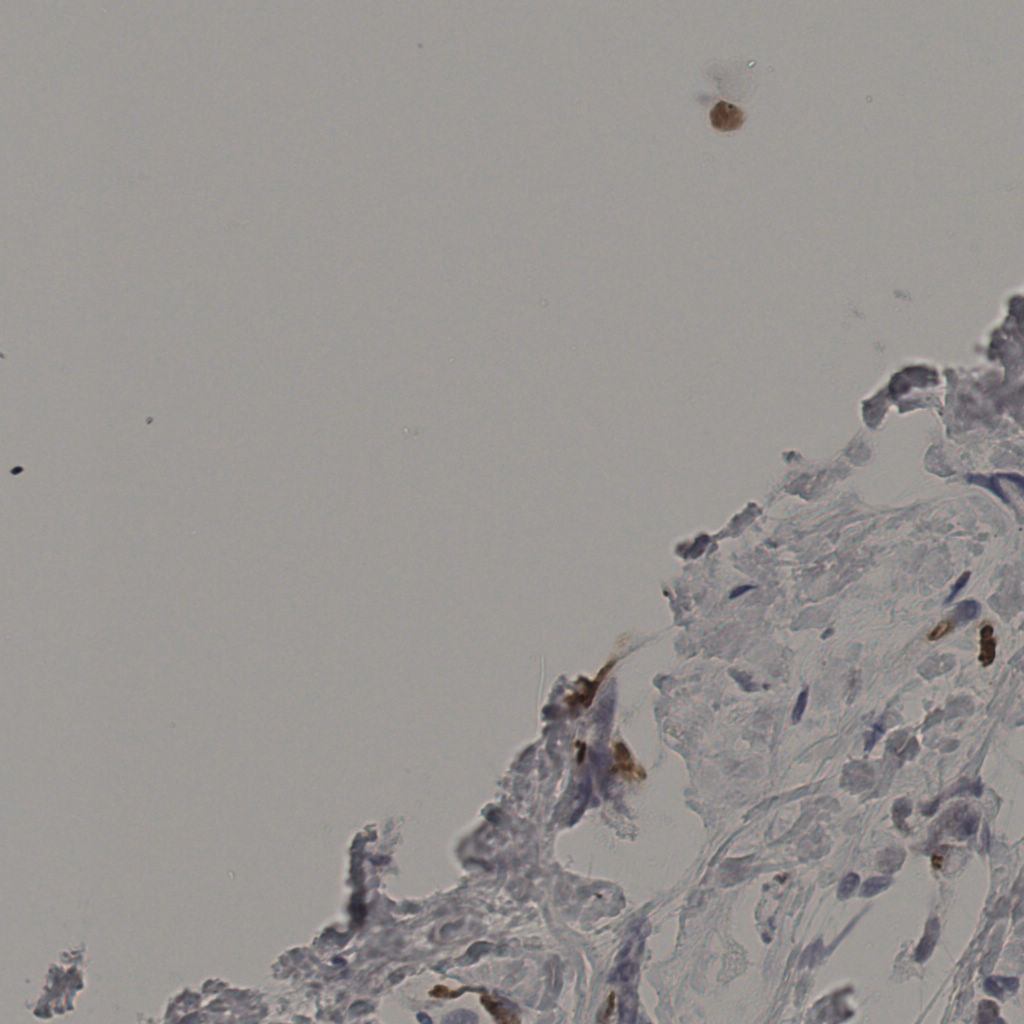

5.31%

Ki67 指数

阴 19502

阳 1093

切片统计

总切片

2970

有效

554

已标记

554

有效率

19%